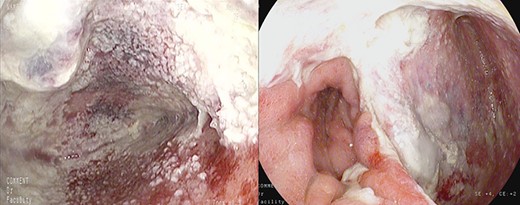

Anastomotic dehiscence was conservatively treated by EVAC therapy, placing the Esosponge in pleural space via an overtube (Fig. 2).